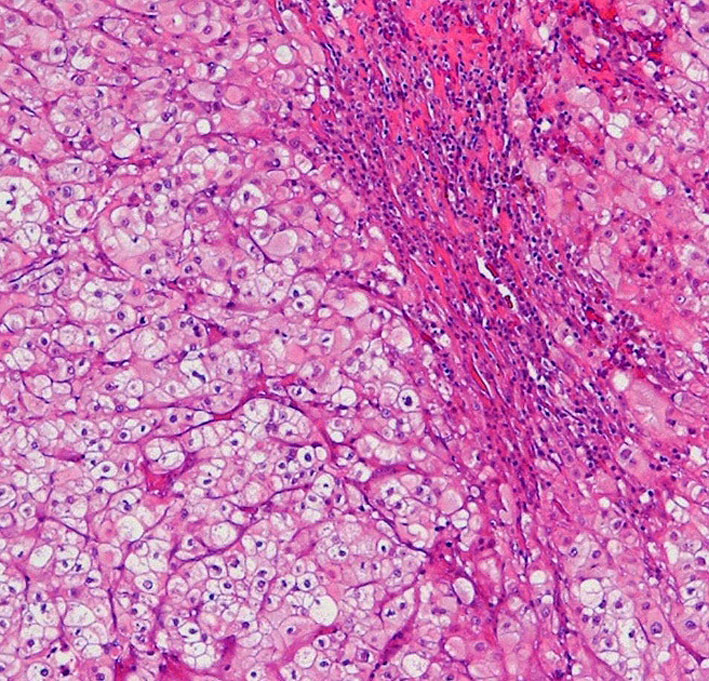

病理像です。軟骨様組織を混在しない純粋な脊索腫です。核を中心にして大きな丸い細胞体には空胞が目立ちます。空胞腫瘍細胞 physaliphorous cellsのシート状配列が特徴的です。左上の写真にわずかに粘液状間質(青く染まるところ)がみえます。